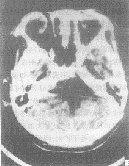

2.3 小脑蚓部I级星形细胞瘤2例 1例由于机器的同心圆伪影重叠,使颅后窝结构显示不清,但第四脑室似有受压改变(图4)。另1例层厚、间隔为10mm平扫时病灶难以发现,在本院改为层厚、间隔5mm,CT平扫时病灶显示。在MR上,小脑蚓部病灶T1W呈稍低信号,T2W呈高信号,约2cm×3cm大小。

图4 小脑蚓部1级星形细胞瘤。机器伪影干扰